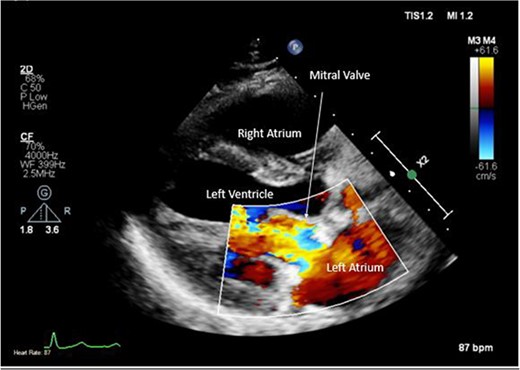

A CTPA was undertaken on Day 2, which excluded pulmonary embolism but confirmed bilateral peri-hilar consolidation and pleural effusions consistent with pneumonia. However, her pulmonary artery was dilated at 32 mm indicative of potential heart failure. On Day 5 of her ICU stay, a transthoracic echocardiogram was undertaken that revealed there to be severe mitral regurgitation including a mobile echogenic mass attached to the underside of the anterior mitral valve leaflet consistent with a vegetation (Figs 1 and 2).

Pre-operative TTE depicting mitral valve with vegetation (labelled).

Pre-operative TTE with Doppler depicting mitral valve with vegetation (labelled).